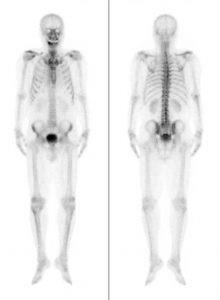

RI検査

微量の放射性同位元素(アイソトープ)で目印をつけた薬を静脈注射したり飲むことにより、その薬が特定の臓器や組織に取り込まれ、そこで放射線(γ線)を出します。その放射線を特別なカメラ(ガンマカメラ)で撮影し、その分布を画像にします。当院では2台の装置が稼動しています。